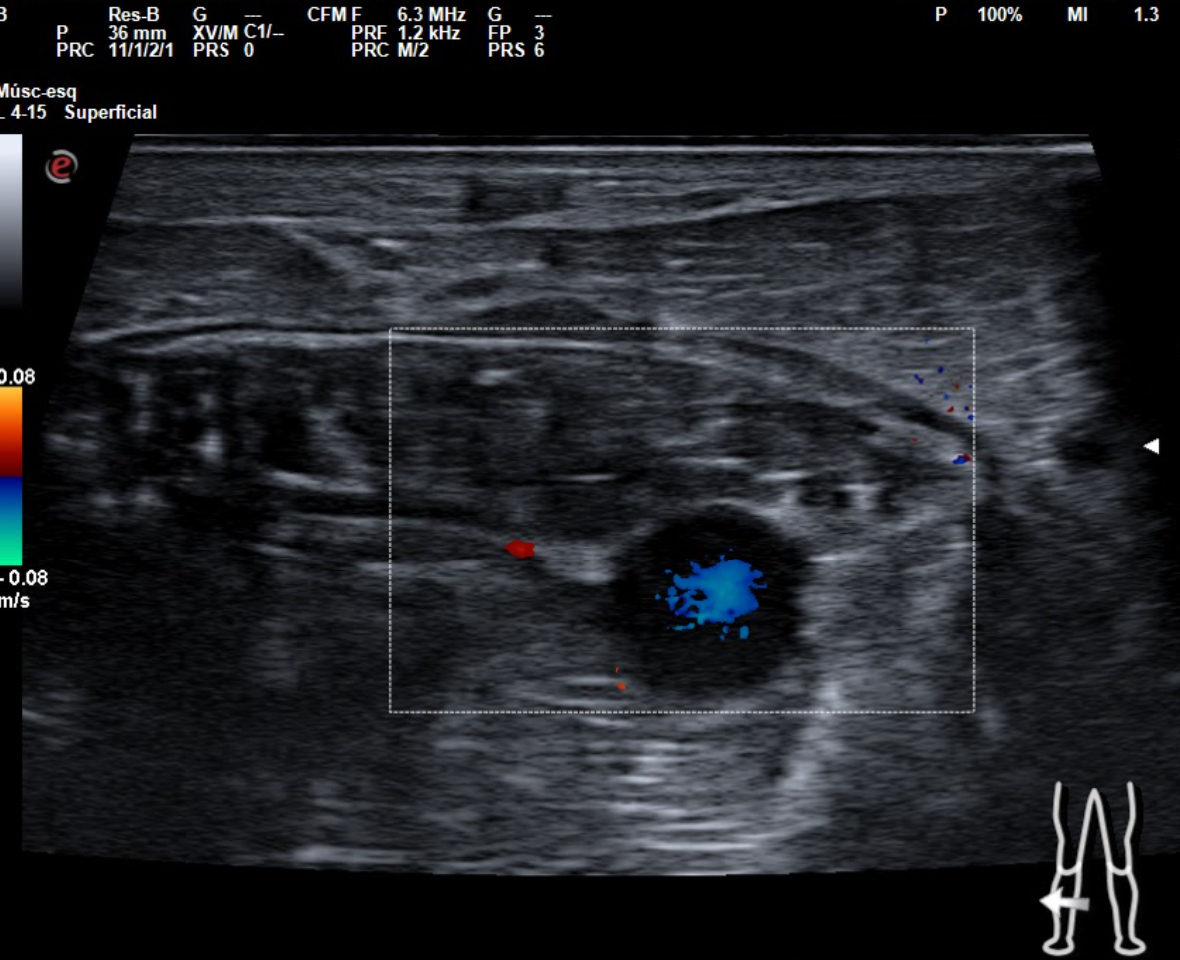

En tendón aquíleo izquierdo se aprecia rotura completa con solución de continuidad de 2 cm localizada a 5,7 cm de su inserción en el calcáneo. Presenta áreas hipoecoicas peritendón que sugieren hematoma secundario. En el aquíleo derecho presenta leve hipoecogenicidad y engrosamiento del tendón sin solución de continuidad que sugiere tendinosis. Importante componente inflamatorio. No datos de TVP. Poplítea y safena externa permeables y compresibles en ambas extremiedades.

Juicio clínico: Rotura completa de tendón de Aquiles izquierdo. Tendinosis aquílea derecha.